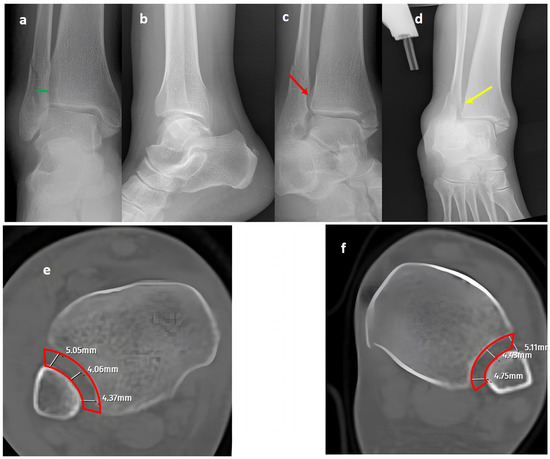

Figure 2.

A Maisonneuve (pronation-external rotation IV) fracture. (a,b) Standard AP and lateral views showing a posterior malleolar fracture with a normal distal tibiofibular (green line) overlap, medial clear space (yellow line), and talocrural angle (blue lines). (c) A mortise view showing an obviously widened distal tibiofibular distance (red arrow), indicating syndesmosis injury. (d) A GAASA view showing lateral displacement of the talus with widening of the medial clear space (red circle) within physiological limits, indicating that the deltoid ligament is intact. However, widening is still evident for the distal tibiofibular distance due to syndesmosis injury (white arrow). (e) A comparison of axial CT images of the injured right ankle and axial CT images of the uninjured left ankle (f) reveals obvious distortion of the whole syndesmosis (red block bows) for the right side. (g,h) Postoperative X-rays showing reduction and fixation of the mortise without the need for the intervention of posterior structures, indicating that the deltoid ligament is intact, consistent with the GAASA image.

Figure 3.

A bimalleolar equivalent (pronation external rotation IV) left ankle fracture. (a) A mortise view showing a high lateral malleolar fracture with normal medial clear space (yellow line) and distal tibiofibular space (green line). (b) A GAASA image showing widened medial clear space (yellow line) and widened distal tibiofibular distance (green line), indicating syndesmosis injury and deltoid ligament injury concomitantly. (c,d) Initial postoperative AP and lateral X-rays showing anatomical reduction after fixation of the lateral malleolus and syndesmosis without repair of the deltoid ligament. (e–h) Axial CT images of both ankles. Although the left-side syndesmosis seems to be widened compared to the right foot, measurements are within normal ranges and do not indicate a syndesmosis injury (red block bows).

In our series, 19 of 36 SER type II and IV cases did not involve syndesmotic injury (Figure 1), which is consistent with the idea that medial and lateral injuries must be carefully assessed before surgical stabilization. These findings highlight that GAASA imaging is particularly reliable in PER injuries, where all medial and lateral structures are disrupted and the fibula is extensively fractured. In such cases, gravitational force causes the talus to exert downward pressure on the distal fibular fragment, producing clear widening of the medial clear space and distal tibiofibular joint [28]. Maisonneuve injuries, not classified by the Lauge-Hansen system, are inherently unstable and require surgical syndesmosis stabilization [29]. In our study, three cases had clear distal tibiofibular widening without pathological medial clear space widening (Figure 2). This contrasts with the cadaveric study by Krahnebühl et al., which reported that stress radiographs are reliable only when deltoid and syndesmotic injuries coexist, but are ineffective for isolated syndesmosis injuries [5]. Our findings suggest that even when the medial malleolus and deltoid ligament remain intact, gravitational force alone can cause lateral fibular displacement, resulting in decreased tibiofibular overlap.

While axial CT images have provided reliable and specific assessments for syndesmosis injuries in previous studies, the diagnostic performance of CT was inferior to GAASA and mortise radiographs in this study [4]. Both inter-observer and intra-observer reliability revealed lower results compared to X-rays. This was an expected result, as the reliability of CT images is acceptable when volume measurement on axial images is performed at 10 mm over the plafond. In our study, the reason for evaluating the CT images subjectively without measurements was to mimic clinical practice scenarios where quantitative measurements are not always feasible. Relying solely on subjective evaluations of widening on axial CT images over the 10 mm plafond is potentially misleading. Even meticulous measurements on CT images do not guarantee accurate efficacy in detecting syndesmosis injuries. Yeung et al. [4] reported excellent inter-observer reliability for CT images in evaluating syndesmosis injuries. However, they found only a 56.4% sensitivity and 91.7% specificity on ROC curves, indicating the limitations of this approach. Despite excellent inter-observer reliability, the syndesmosis itself may not appear widened if unstressed or if any structures block the fibula from reducing to its proper position in CT imaging. When in a reduced position, the tibiofibular distance could appear within normal ranges on CT images and mortise radiographs (Figure 3) [1]. Researchers have proposed using direct arthroscopic visualization of the syndesmotic joint as a more precise diagnostic approach, as no imaging modality is perfect at detecting syndesmosis injuries [33]. From this perspective, some authors have utilized both conventional and dynamic ankle CT scans performed under forced external rotation, dorsiflexion, and axial loading in various foot positions. Their results revealed that applying stress significantly improves the diagnostic performance for detecting subtle syndesmotic instability [20,21]. To reduce radiation exposure and minimize the pain caused by stress applied to the ankle, ultrasonography (USG) has been utilized for the detection of ankle ligament injuries. It has been shown that ultrasound has good to excellent diagnostic value for complete discontinuity of the anterior talofibular ligament (ATFL) and the anterior inferior tibiofibular ligament (AITFL). Compared with static ultrasound, dynamic ultrasound demonstrated inferior diagnostic value for detecting complete discontinuity of the AITFL [34]. Although USG has high sensitivity and specificity in identifying ligamentous injuries such as the ATFL and AITFL, its role in assessing syndesmosis stability remains unclear. This is because the syndesmosis complex comprises five anatomical components, and in most cases, instability occurs only when all five structures are disrupted [31,35]. Furthermore, from an orthopedic surgeon’s perspective, the use of USG may not always be feasible or practical due to its operator-dependent nature, limited availability in some clinical settings, and the requirement for significant expertise to ensure accurate and reliable results.